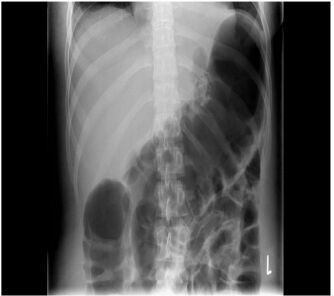

8. 63歲男性,因為鬱血性心臟衰竭住院,BMI 42 kg/m², 入院時氧氣濃度(SaO2)為75% , 血壓為140/80 mmHg。胸部X光顯示肺水腫,心跳數為136/min,同時合併出現非持續性心室頻脈(non-sustained ventricular tachycardia)。心臟超音波顯示兩心室(左右心室)功能皆不全,左心室射出分率為15%, 實驗室檢查顯示,腎功能: creatinine clearance 80 ml/min, NTproBNP 3000 pg/ml, 右心導管顯示低心輸出率 (cardiac index of 1.5 l/min/m²),肺動脈楔壓(PCWP)為20 mmHg。下列心衰竭藥物的注射選擇何者最為恰當? (A) Dobutamine 1~2 ug/kg/min 靜脈注射。 (B) Dopamine 10 ug/kg/min 靜脈注射。 (C) Norepinephrine 3ug/kg/min 靜脈注射。 (D) Levosimendan 0.10 ug/kg/min 靜脈注射。 (E) Dopamine 2 ug/kg/min 靜脈注射。